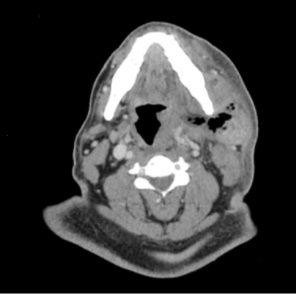

A 50 yo M presents to the ED w/ dental pain and facial swelling, worsening over the last 2 weeks. He denies fever, voice changes or dysphagia. On exam his temp is 99.1, HR 122 and spo2 98%. He is nontoxic appearing, has no trismus or drooling, but there is noted erythema and swelling of the L cheek down to the level of the clavicle. A CT is obtained and shown below. What's the diagnosis? (scroll down for answer)

Answer: Gas producing facial cellulitis and abscess of the L masticator space (with concern for early Ludwig's angina)

- Diagnosis

- CT of face/neck with contrast